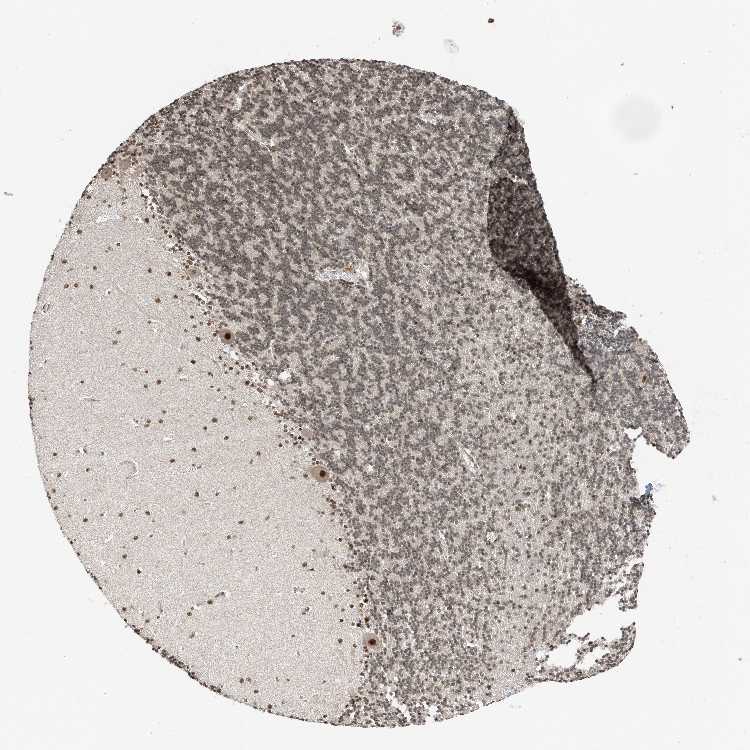

CEREBELLUM - Antibody stainingi

Antibody staining in the annotated cell types in the current human tissue is reported as not detected, low, medium, or high, based on conventional immunohistochemistry profiling in selected tissues. This score is based on the combination of the staining intensity and fraction of stained cells.

Each image is clickable and will lead to virtual microscopy that enables deeper exploration of all samples and also displays staining intensity scores, fraction scores and subcellular localization as well as patient and tissue information for each sample.

Antibody HPA023924Antibody HPA031526

Purkinje cells MediumHigh

Cells in granular layer MediumMedium

Cells in molecular layer Not detectedMedium